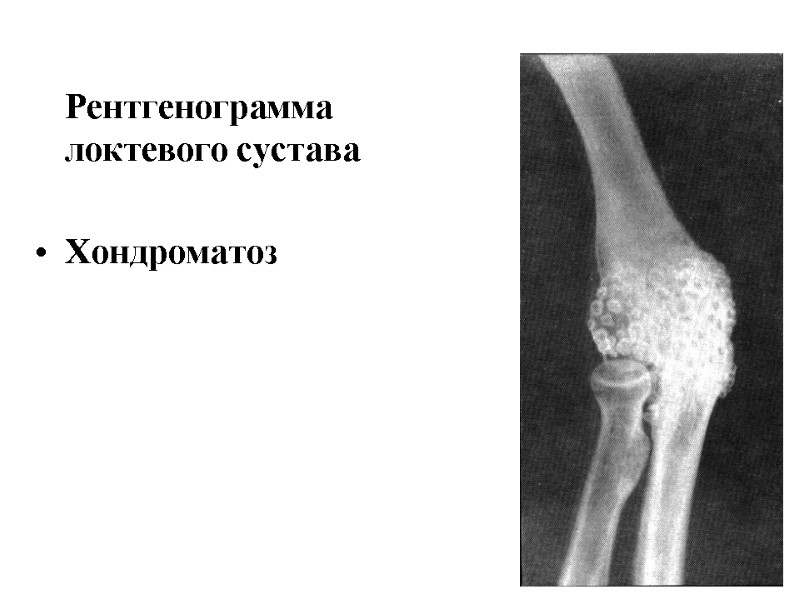

Рентгенограмма локтевого сустава Хондроматоз